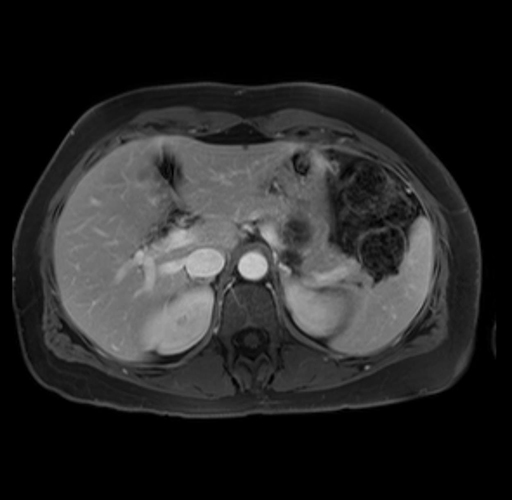

Imaging Analysis

Look through the patient's CT scan to identify any areas of concern for the necessary procedure.

Based on your CT findings, which issue(s) are present and would give reason for "planned slowing down moment(s)" in this case?